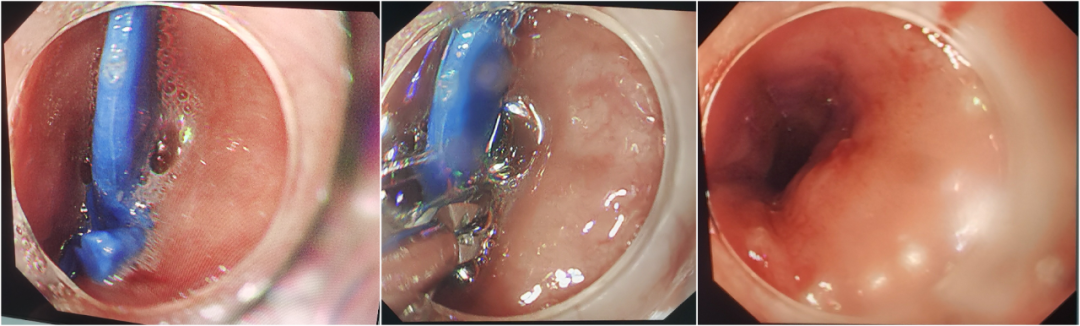

在镇静镇痛保障下,消化医学中心医师通过内镜精准定位,轻柔操作,仅15分钟就完整取出玩具恐龙。术中患儿生命体征平稳,几乎没有痛苦,食管黏膜损伤轻微、几乎无出血,术后很快恢复正常进食与活动。